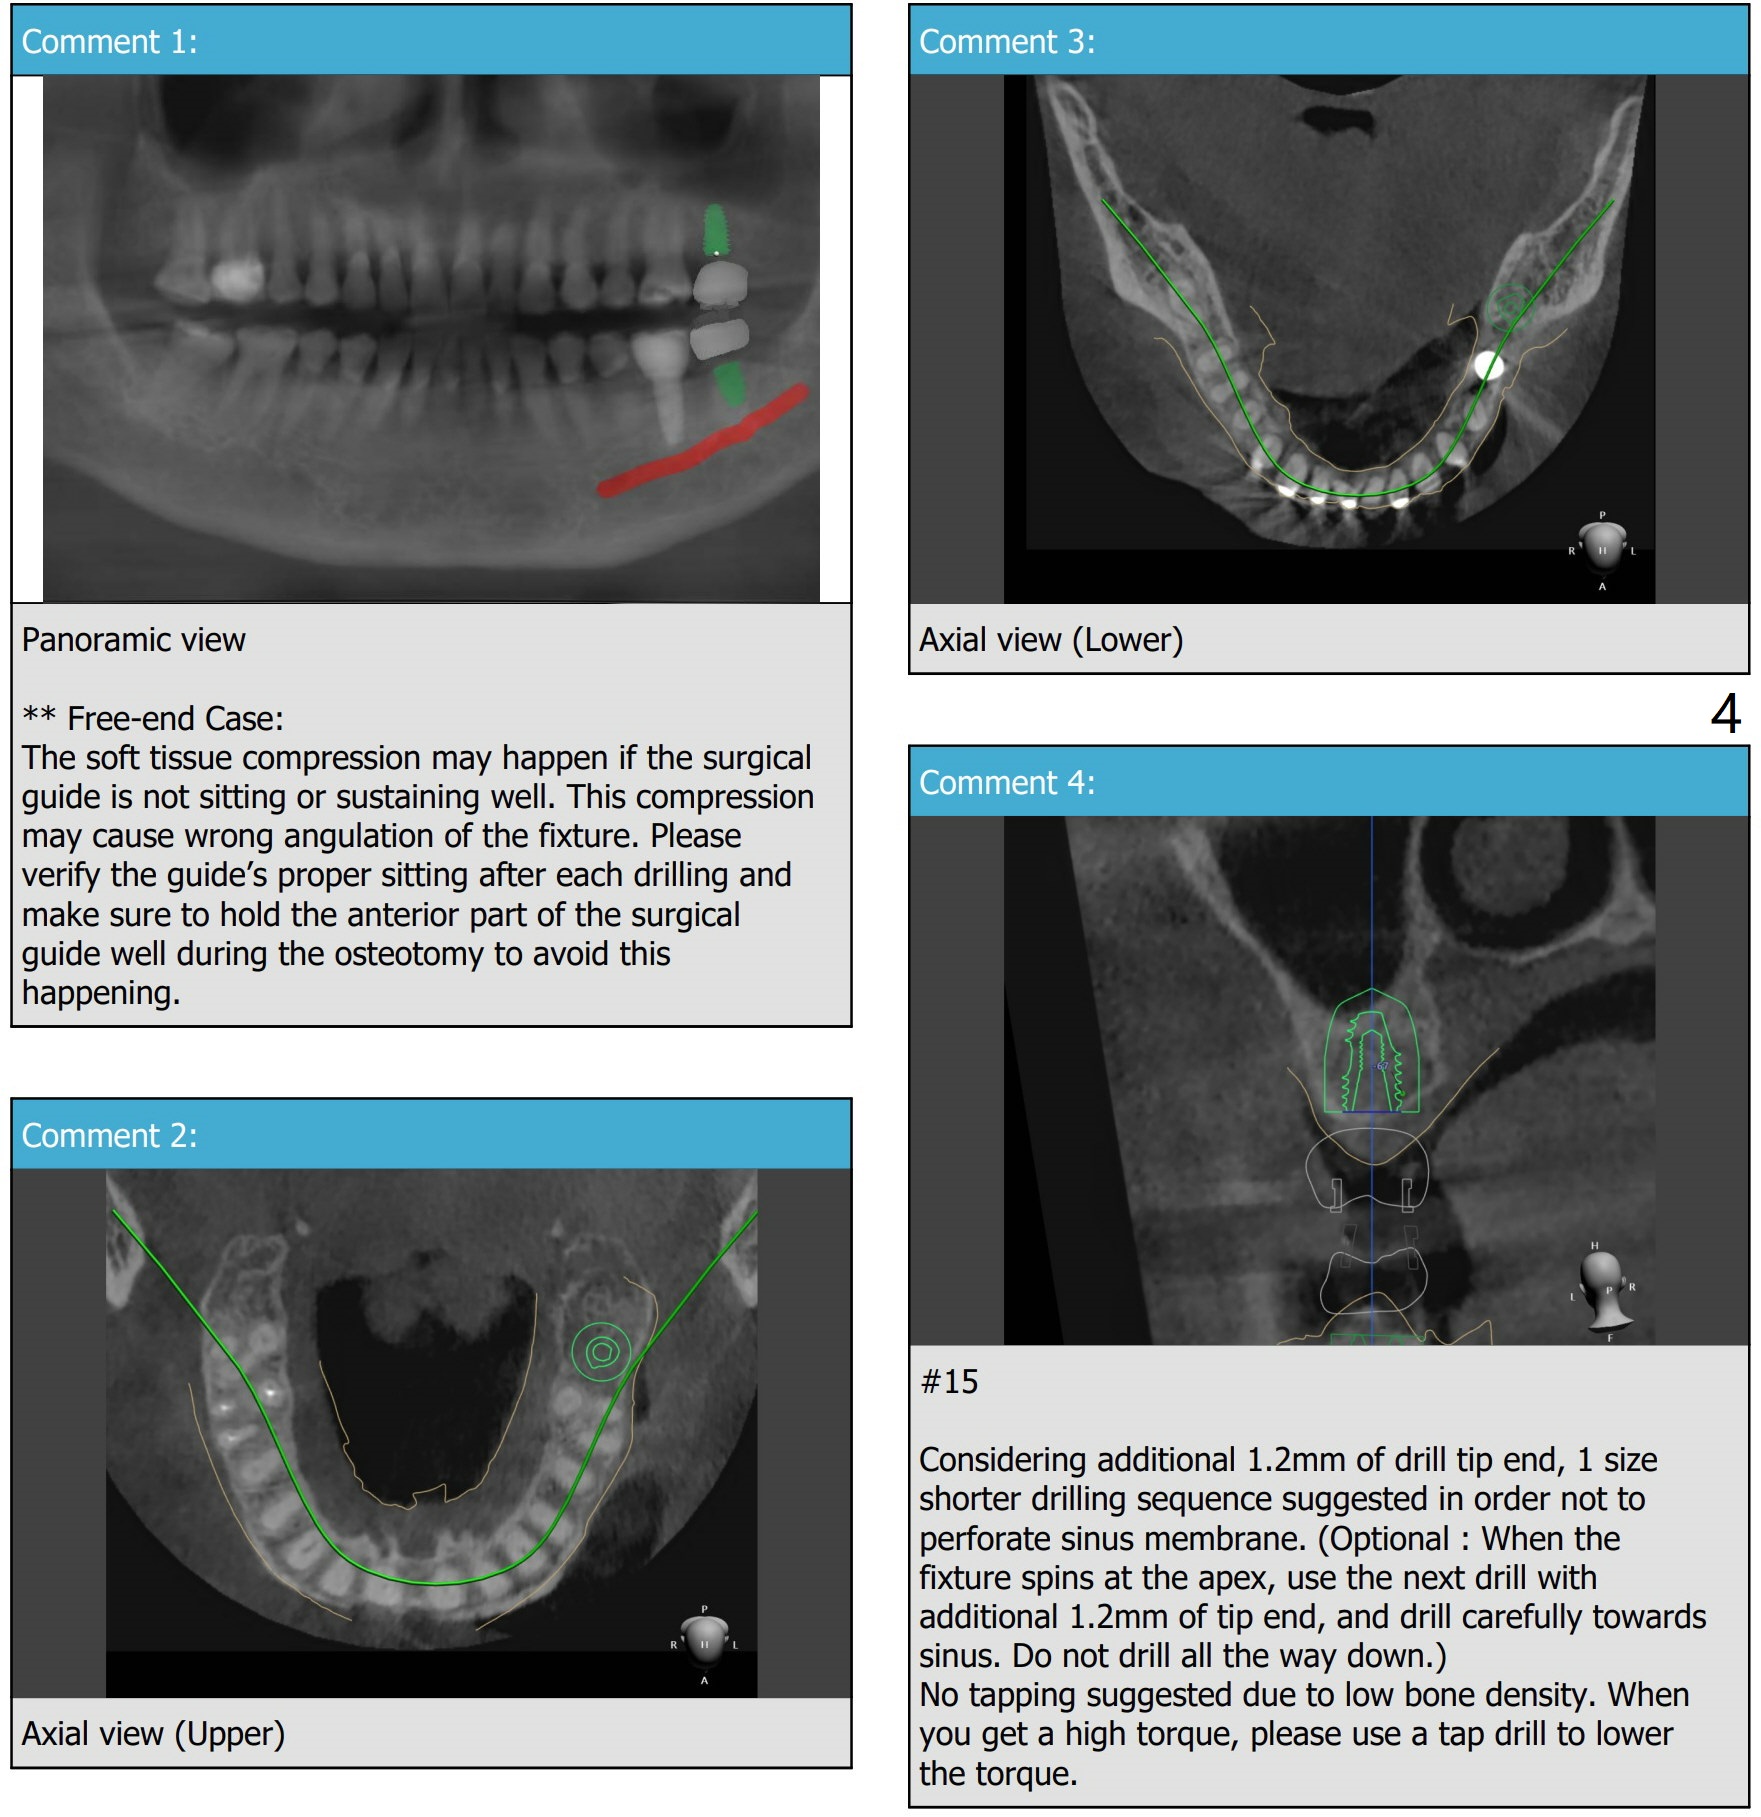

Short Implants

A 73-year-old woman

Xin Wei, DDS, PhD, MS 1st edition 03/15/2021, last revision 04/10/2021